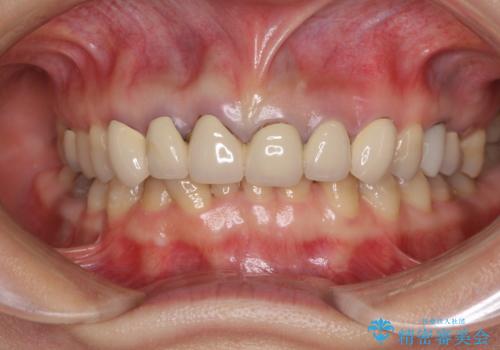

セラミッククラウン装着後は、とても自然な口元に仕上がりました。